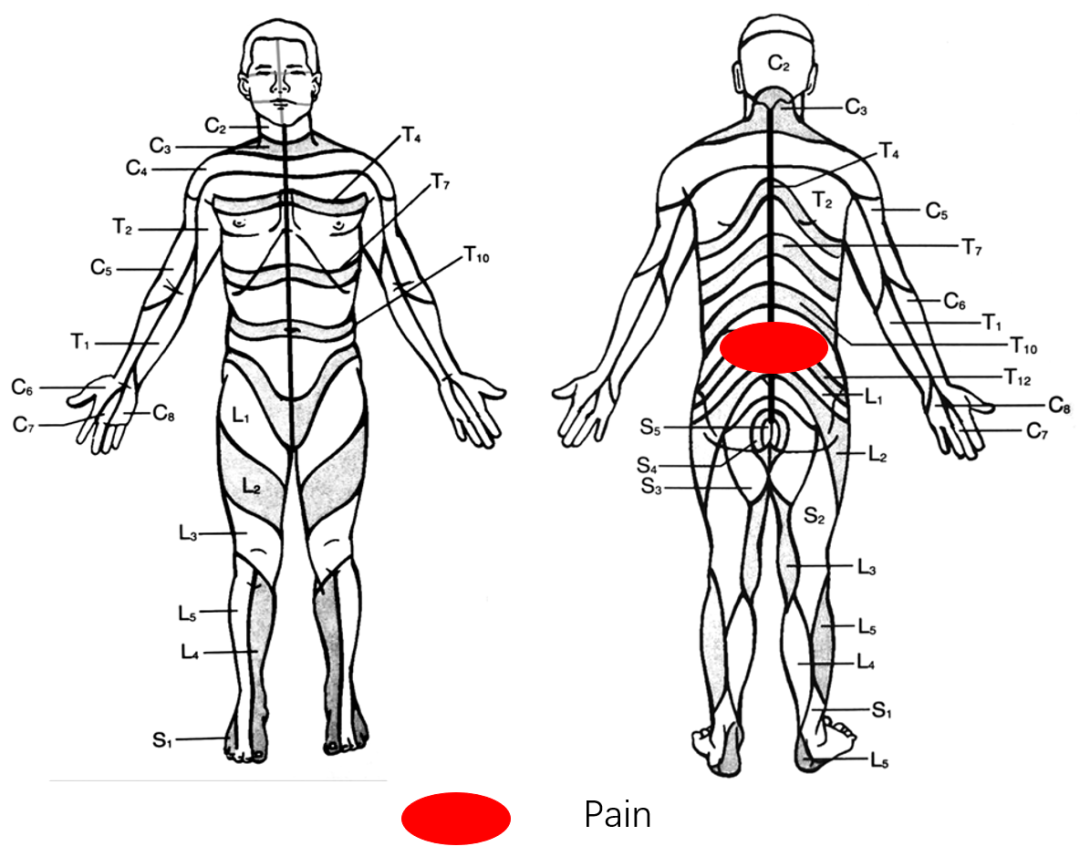

腰背痛2年,加重伴腰部后凸不能直立半年

Diagnosis:

腰椎侧后凸畸形

腰椎陈旧性压缩性骨折(L4)